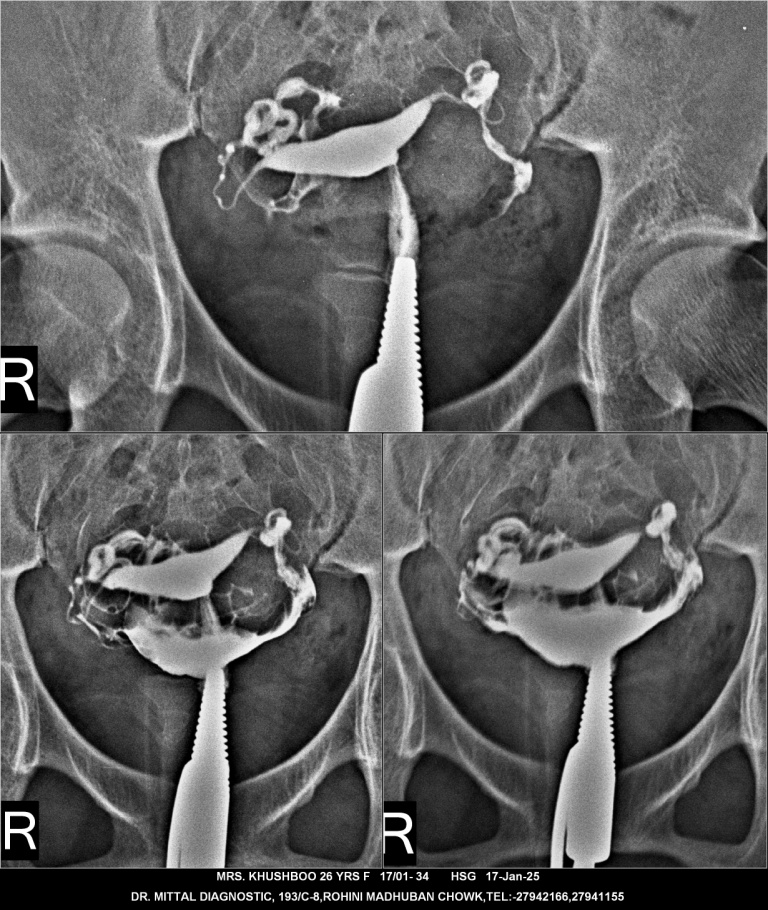

Hsg test in delhi Hsg test in rohini Hsg avalable in rohini A hysterosalpingogram (HSG) is an X-ray procedure that examines the uterus and fallopian tubes. It uses a special dye and low-dose X-rays to produce images of the reproductive organs.